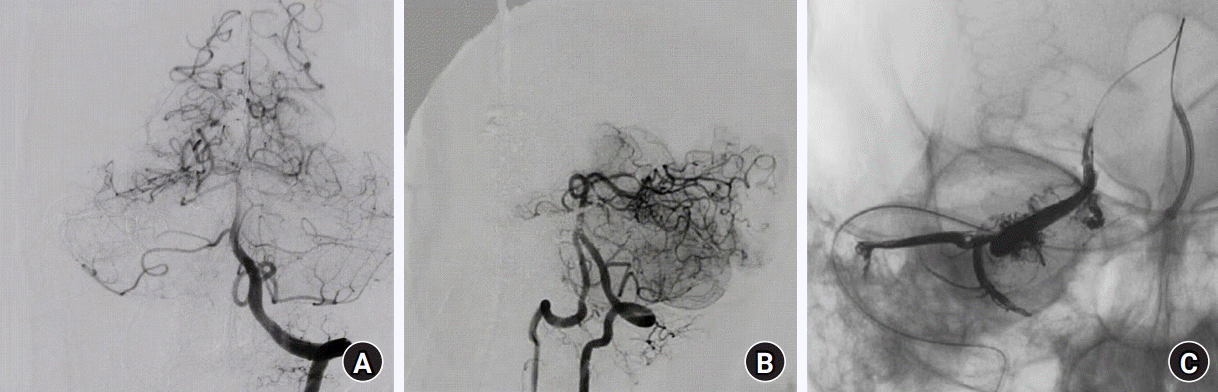

In preparation for interventional surgery, the tissue was disinfected. Heparin was administered before puncture to ensure that the activated coagulation time (ACT) remained > 250 s, with additional heparin dosages adjusted based on the ACT throughout the procedure. The right femoral artery and vein were punctured and 6 F catheter sheaths were inserted into both the artery and vein. With the assistance of a cardiovascular physician, an ECG electrode was threaded into the right ventricle through the right femoral vein. Correct positioning was confirmed under DSA guidance, and the pacemaker settings were adjusted to ensure heart capture at minimum levels. Under DSA guidance, the right internal jugular vein was punctured and a 6 F catheter sheath was inserted. Using guidewire assistance, a catheter was then inserted into a suitable drainage vein. After connecting the defibrillation electrode to the defibrillator, rescue drugs, such as esmolol, lidocaine, amiodarone, epinephrine, norepinephrine, and nitroglycerin, were prepared along with a transvenous injection of 100 mg phenobarbital sodium. Room temperature was lowered to 18°C, 300 ml of normal saline at 4°C were injected intravenously, and an ice cap was placed on the head to maintain core temperature around 35°C for brain protection. At this point, the IBP was 87/54 mmHg (Fig. 2A) and cerebral oxygen saturation was 75% on the left and 74% on the right side. The pacing rate was set at 180 bpm and RVP was initiated. When the IBP waveform had flattened, the systolic IBP was maintained between 30 and 40 mmHg (Fig. 2B, Supplementary Video 1). Despite ineffective cardiac contractions, a significant amount of forward blood flow persisted. The surgeon then injected embolic agents at the target site, which quickly coagulated at the lesion. Ventricular pacing ceased after 30 s and IBP returned to 95/50 mmHg within 3 s, with 74% cerebral oxygen saturation on both sides. The same procedure was repeated 3 min later with RVP and the embolic agent injection. Following rapid coagulation, ventricular pacing was discontinued, IBP was restored to 113/62 mmHg, and cerebral oxygen saturation remained at 73% on both sides. The entire procedure lasted 8–10 min and proceeded smoothly. Following two rounds of RVP, repeated multiangle angiography revealed satisfactory embolization (Figs. 3A–C, Supplementary Figs. 3 and 4). Prior to the end of surgery, the ABGA indicated the following: pH 7.44, PaCO2 41 mmHg, glucose 7.6 mmol/L, lactic acid 1.2 mmol/L, hematocrit 40%, base excess 3.6 mmol/L, and total hemoglobin 13.2 g/dl. During the operation, 2,500 ml crystalloid fluid was infused along with 10 mg of furosemide, resulting in a urine output of 950 ml, minor bleeding, and dilated and round bilateral pupils. Postoperatively, cerebral oxygen saturation (left: 75%, right: 75%) was maintained, and the patient was transferred to the neurosurgical intensive care unit with a tracheal catheter for further treatment.